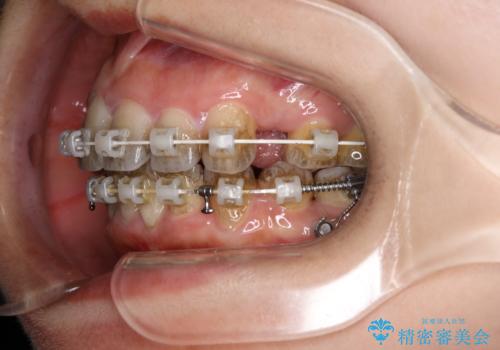

エアフローとは

エアフローワンは、特殊なパウダーを混ぜた水を水面にジェット噴射することでバイオフィルム(プラーク)・ステイン(着色)・早期歯石を天然歯やインプラント周囲から除去することが可能な歯面清掃器具です。

従来の荒い研磨剤などを用いた歯面への負担が大きいクリーニングとは異なり、歯質の負担を最小限にした歯面清掃と歯周ポケット内のメンテナンスを行えます。

エアフローワン60分コース¥14300

(前歯から奥歯)

エアフローワン30分コース¥8800

(前歯メイン)

※歯石や着色の量により範囲は変わります。